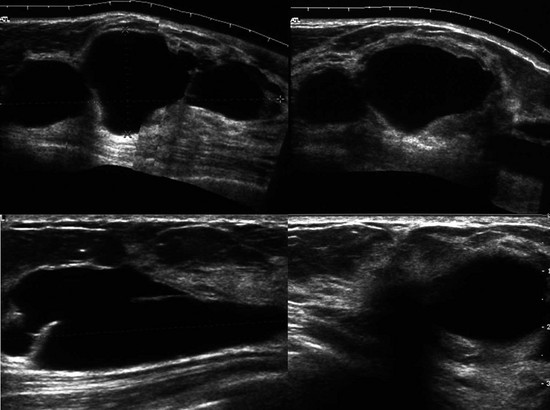

FIGURE 8-4 Metastatic Lesions in the Breasts.

This 47-year-old woman presented with a palpable lump in the right breast (marker). There are multiple circumscribed masses in both breasts. Note that the masses are primarily located in the retromammary fat and even in the axillary fat. US shows a solid hypoechoic mass with microloculated margins. Ultrasound-guided core biopsy samples were black in appearance. The patient subsequently gave a history of ocular melanoma 5 years earlier. Biopsy showed metastatic melanoma.